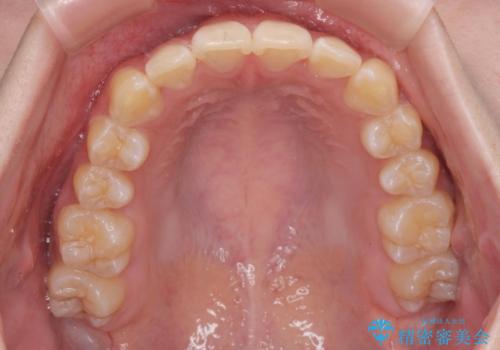

前歯のがたつき気になる。インビザラインモデレート

- 前歯のがたつきが気になるとの事で来院。

マウスピース矯正希望でしたのでインビザラインモデレートで治療を行いました。

がたつきが無くなり満足して頂けました。